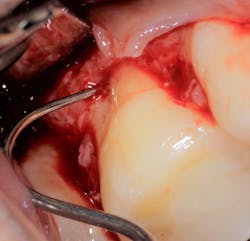

Saving compromised multirooted teeth with root amputation can often be successful, but the technique is sensitive and complex. Proper case selection is essential, and considerations include the following:

There is sufficient bone support around the remaining roots (at least 50% or more is needed) along with sufficient coronal tooth structure (figure 3).How does root amputation compare with other surgical procedures?